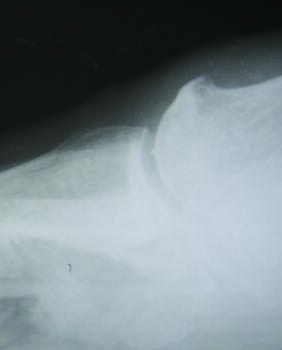

Stage 1. In this stage of the classification system only 30 to 40 degrees of dorsiflexion is available for the hallux to dorsiflex passively.17 There will be some dorsal spurring on radiograph, with minimal narrowing of the joint space. The patient will describe intermittent mild pain, typically at the end stage of first MPJ range of motion. These clinical and radiographic findings are consistent with early hallux limitus.

Stage 2. In stage 2, there is more dramatic loss in dorsiflexion at the first MPJ with only 10 to 30 degrees of dorsiflexion remaining, which can make ambulation difficult as well as painful.17 Radiographically, a more extensive dorsal osteophyte will be seen than in stage 1, with further decrease in the joint space. This stage now represents a structural hallux limitus.

Stage 3. In stage 3, the patient has lost nearly all motion in the first MPJ, now with less than 10 degrees of dorsiflexion remaining, and movement of the joint to the end range of motion causes the patient significant pain.17 Radiographically, there will be significant joint space narrowing, joint destruction, and with possible sesamoid change. This stage by definition constitutes a hallux rigidus.

Stage 4. This stage is similar to stage 3, except any motion at the first MPJ causes the patient pain.17 Radiographs will demonstrate arthrosis of the joint, with osteophytic changes of both the metatarsal head, and base of the proximal phalanx.

Radiographic findings may be subtle or negative in the early phases of the condition.18 As the condition progresses, radiographic findings may reveal joint narrowing, thinning of articular surfaces, osteophytic changes of the base of the proximal phalanx, spurring of the metatarsal head, and possible fracture fragments/loose bodies. If previous injury to the sesamoids occurred, there may be degenerative changes there as well.18